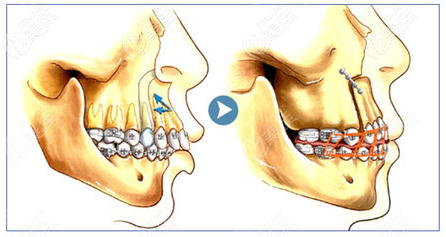

上顎骨突出矯正手術(shù)屬于四級頜面整形手術(shù),具有一定的風(fēng)險,為了降低手術(shù)風(fēng)險,建議選大型正規(guī)具備四級頜面磨骨資質(zhì)的醫(yī)院和醫(yī)生進(jìn)行手術(shù)。